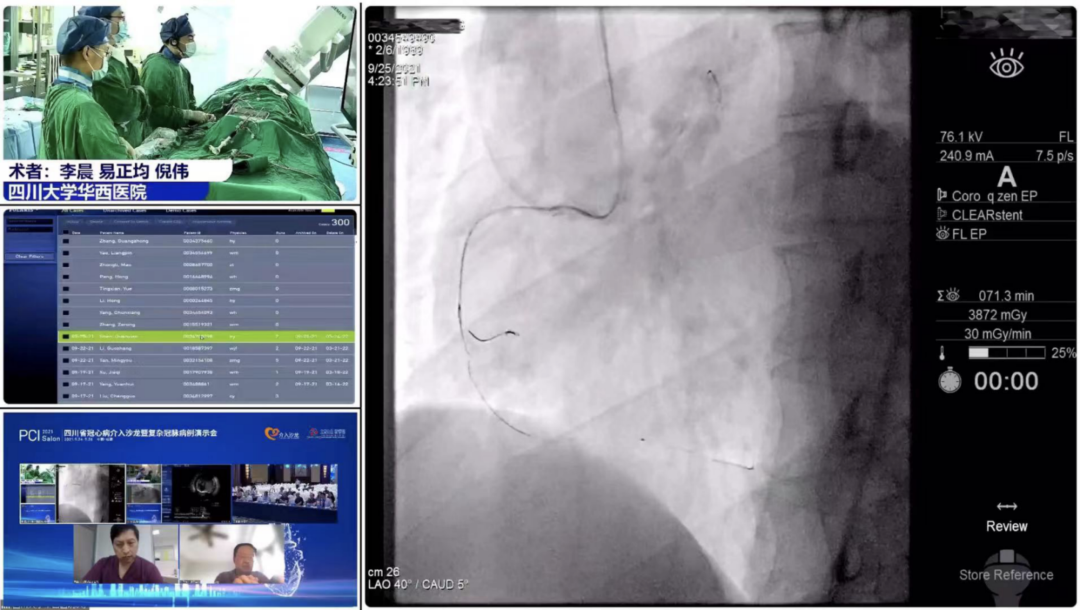

9月25日,大会隆重开幕,大会执行主席、四川大学华西医院贺勇教授主持,大会创始人及名誉主席、四川大学华西医院心内科黄德嘉教授,北京力生心血管健康基金会管廷瑞理事长,大会主席、四川大学华西医院陈茂教授,大会创始人及名誉主席东莞康华医院贾国良教授等多位专家领导分别以线上、线下参会形式共同出席开幕式,并为大会开幕致辞。随后,来自全国多地的冠脉领域资深术者通力配合,带来了11场极具难度和技巧的复杂冠脉病例手术演示及微课讲座。同期进行的护理及技术人员论坛、冠脉腔内影像与生理学论坛、冠心病诊疗论坛、降脂治疗论坛&心衰药物进展论坛、血栓抽吸、药物球囊、愈合型支架等专题学术内容应接不暇、精彩纷呈。